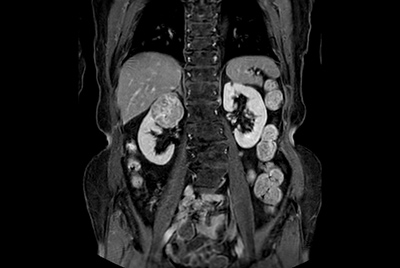

Multi-phase, contrast-enhanced renal imaging